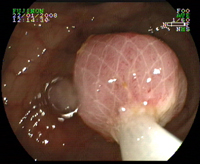

Injection sous muqueuse sous le polype

Polype sessile

Polype sessile du colon

Polype sessile dysplasique